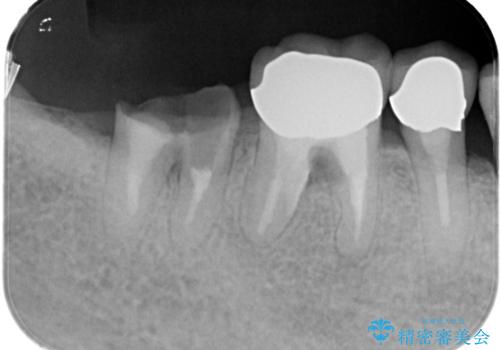

- 「他院で治療した被せ物が外れた」を主訴に来院された患者様です。診査診断を行い歯の保存が困難だったため抜歯後、インプラントで治療しました。

インプラントを入れるためには十分な骨の高さと幅が必要です。術前に検査を行い必要であれば別途、骨や角化歯肉を増やす治療も行う事があります。